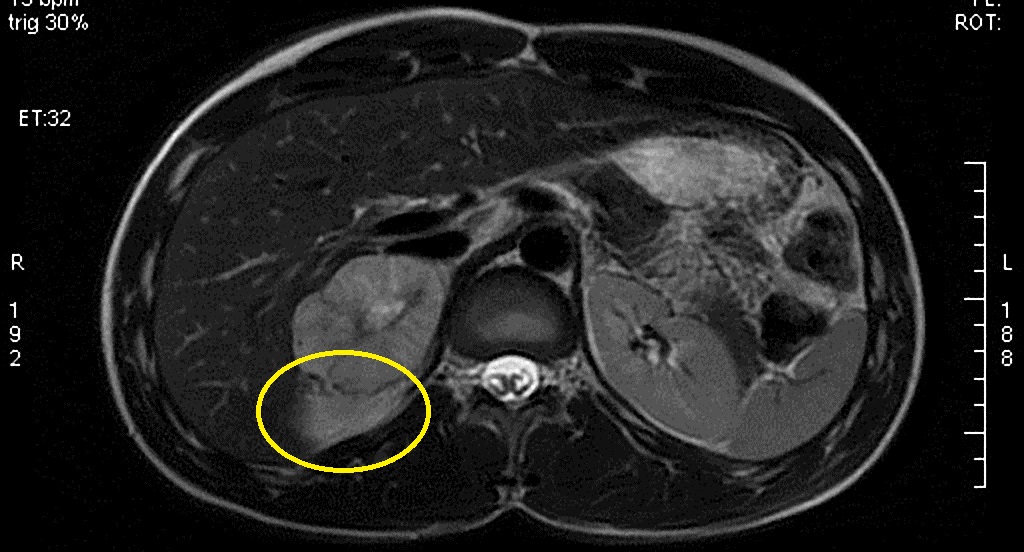

Фотографии и схемы анатомии надпочечников